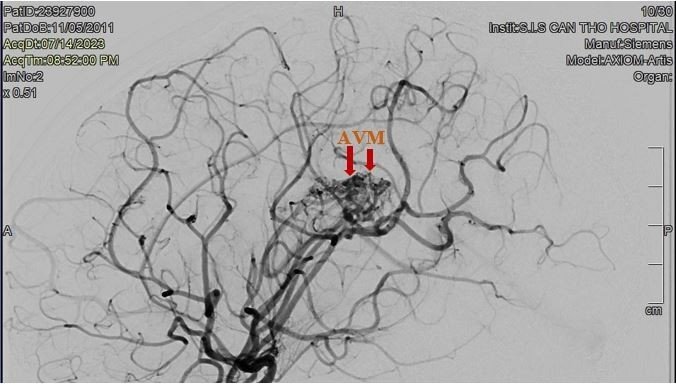

Khi vào Bệnh viện Đa khoa Quốc tế S.I.S Cần Thơ, bệnh nhi bị đau đầu nhiều và yếu nửa người trái. Theo BS. CKII Ngô Minh Tuấn – Trưởng khoa CĐHA – TDCN, Bệnh viện S.I.S Cần Thơ, bé A. vào viện đã bị xuất huyết não do vỡ dị dạng thông động tĩnh mạch não (AVM) và có túi giả phình lớn (kích thước 3x3mm) trong búi dị dạng, tình trạng rất nguy hiểm. Bệnh nhi đã được ê-kip can thiệp thành công, giảm lưu lượng của dị dạng và đặc biệt là tắc được túi giả phình cho bé.

“Sau can thiệp và chăm sóc tích cực khoảng 1 tuần, tình trạng bé A. đã ổn định, còn yếu nhẹ chân trái, tiếp tục được tập vật lý trị liệu để phục hồi chức năng. Búi dị dạng mạch máu của bé A. đã giảm đáng kể, tuy nhiên cần chụp DSA mạch máu não sau vài tháng khi tình trạng bé ổn định để đánh giá tình trạng của ổ dị dạng. Nếu cần thiết sẽ tiến hành can thiệp lần 2 hoặc bắn tia gamma để triệt tiêu búi dị dạng” – BS Tuấn cho biết thêm.